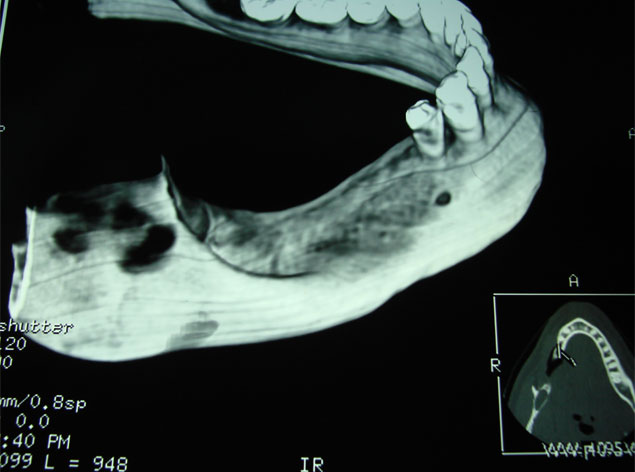

Son injertos del propio paciente extraídos del mentón o rama ascendente, destinados a aumentar la anchura del hueso indicados en maxilares con achura inferior a los dos milímetros.

Se deben fijar siempre con tornillos de 1.2 o 1.6 mm de osteosíntesis.

Terminada la reconstrucción ósea, es necesario esperar de 3 a 6 meses para la colocación de los implantes